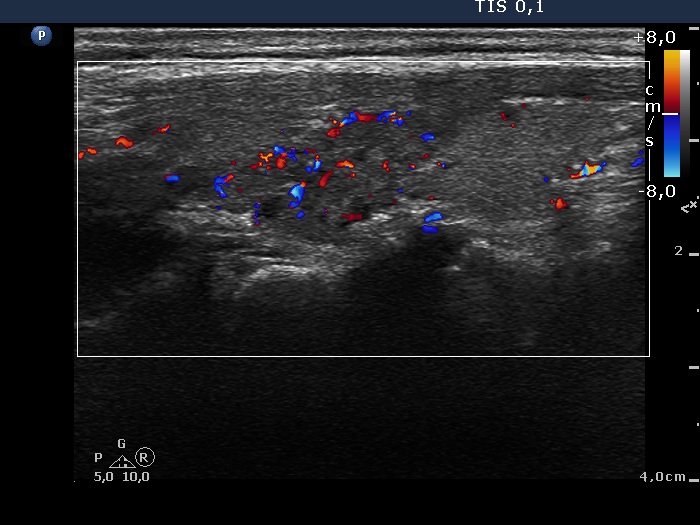

Discrete lesion or nodule in Hashimoto's thyroiditis - case 5 (1073) (ultrasonographic picture 4)

Right lobe, longitudinal view, color Doppler mode.